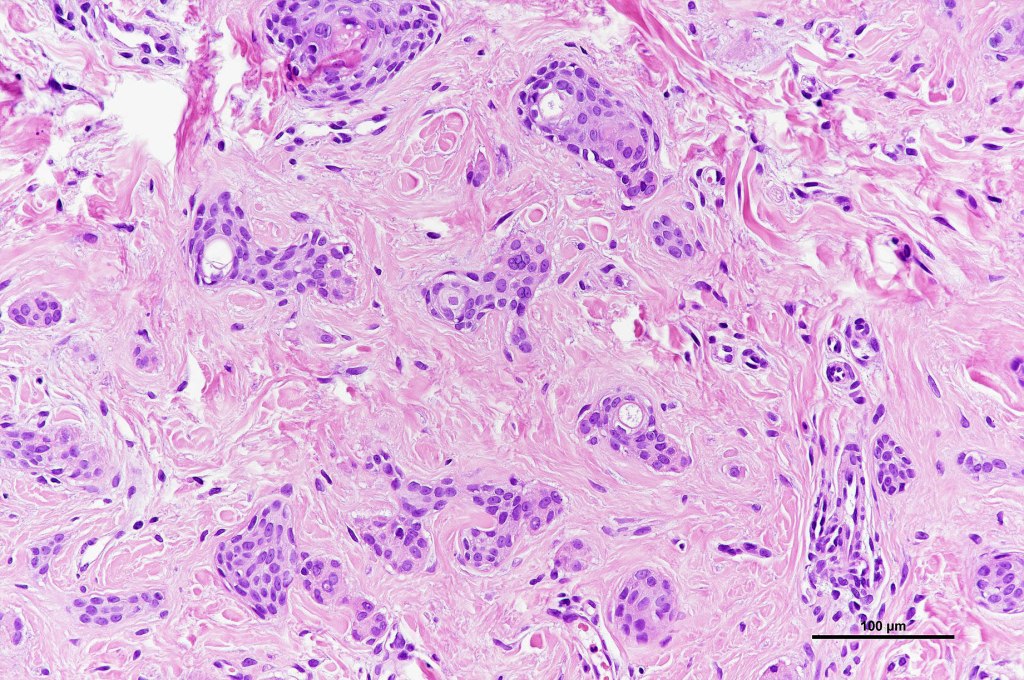

Histological features

•Dermal lesion composed of epithelial stands & ducts dispersed in a fibrous stroma

•Tadpole configuration- ducts with epithelial strands

Intracytoplasmic lumina

•Absence of pleomorphism or mitotic activity